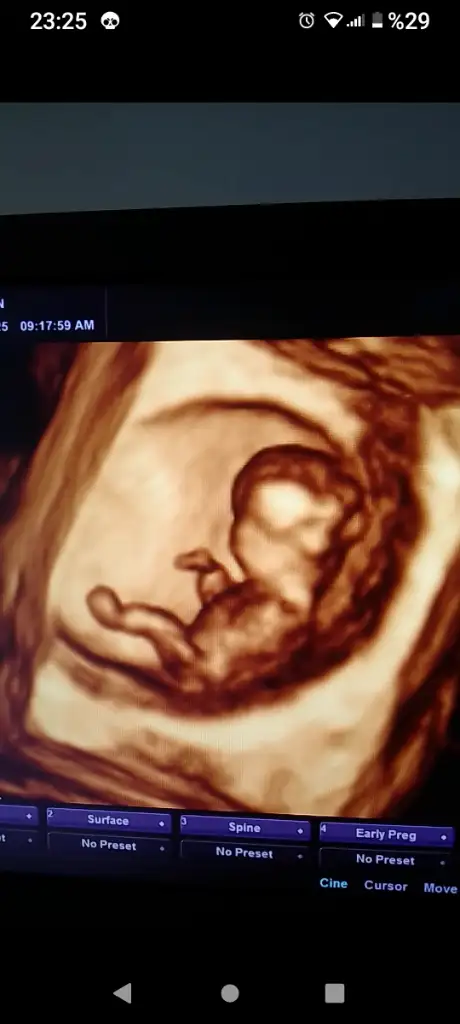

Tam 12. Haftadayız. Bugün doktor erkek gibi dedi ama kesin konuşmadı. Açıkçası ben de kafasını ense yapısını çene yapısını erkeğe benzetiyorum. Bir de nub a göre duruşuna göre erkek gibi dedi ama soru işareti ile.

Kesin erkek diyeceğim bi bakıyorum görüntüye 3 çizgi var bacaklarının o tarafta.Kızlarda 3 çizgi oluyormuş , o yüzden erkek mi emin olamıyorum kafam karışıyor anlayan biri varsa bakabilir mi